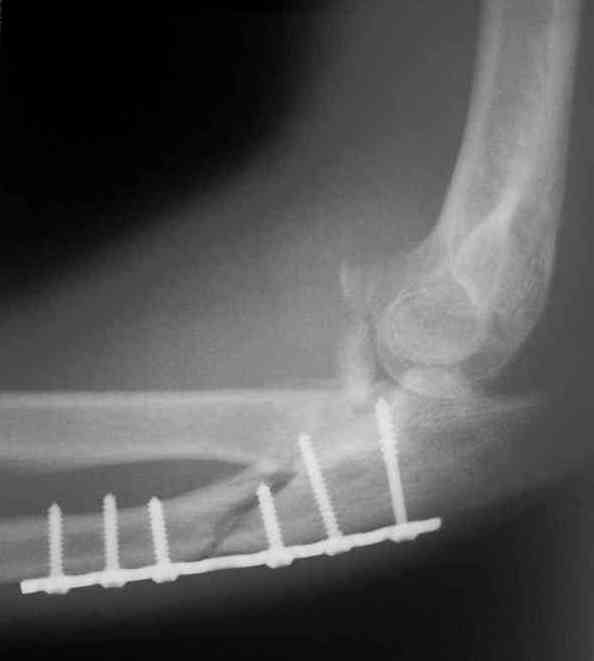

Больной был прооперирован.Протеза головки лучевой у нас нет. Решили с локтевой костью пока ничего не делать. Выполнили операцию по востановлению связочного аппарата локтевого сустава(см.схему)- модфикация метода W.E.Spring,сухожилие мы фикстровали к винту на локтевой.

Естественно ревизия сустава и удаление рубцово-хрящевидных тканей.Затем наложили аппарат Илизарова с шарнирами. Первые 2 дня сустав был фиксирован трансартикулярно 2-мя спицами, затем спицы удалили. И больной начинает движения в аппарате.

Прилагаюся послеоперационные рентгенограммы.

Планиуем аппарат на 3-4 нед.